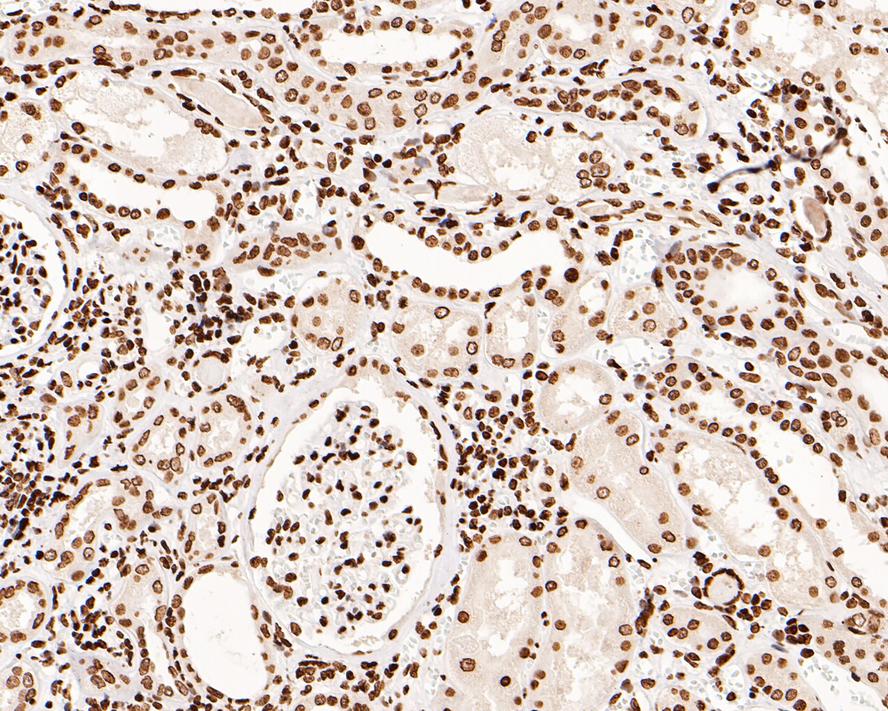

ET1607-34_5.jpg Fig5: Immunohistochemical analysis of paraffin-embedded human kidney tissue with Rabbit anti-Phospho-JAK2 (Y1007 + Y1008) antibody (ET1607-34) at 1/500 dilution.

The section was pre-treated using heat mediated antigen retrieval with sodium citrate buffer (pH 6.0) for 2 minutes. The tissues were blocked in 1% BSA for 20 minutes at room temperature, washed with ddH2O and PBS, and then probed with the primary antibody (ET1607-34) at 1/500 dilution for 1 hour at room temperature. The detection was performed using an HRP conjugated compact polymer system. DAB was used as the chromogen. Tissues were counterstained with hematoxylin and mounted with DPX.